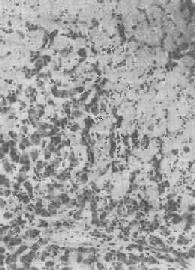

脾中央动脉玻璃样变

图1-20 脾中央动脉玻璃样变

中央动脉管壁明显增厚,呈玻璃样均质状,管腔变窄

2.血管壁玻璃样变:这种改变常见于高血压病时的肾、脑、脾及视网膜的细动脉。此时,可能是由于细动脉的持续性痉挛,使内膜通透性增高,血浆蛋白得以渗入内膜,在内皮细胞下凝固成无结构的均匀红染物质。此外,内膜下的基底膜样物质增多。这些改变使细动脉的管壁增厚、变硬,管腔变狭,甚至闭塞(图1-20),此即细动脉硬化症(arteri-olosclerosis),可引起肾及脑的缺血。